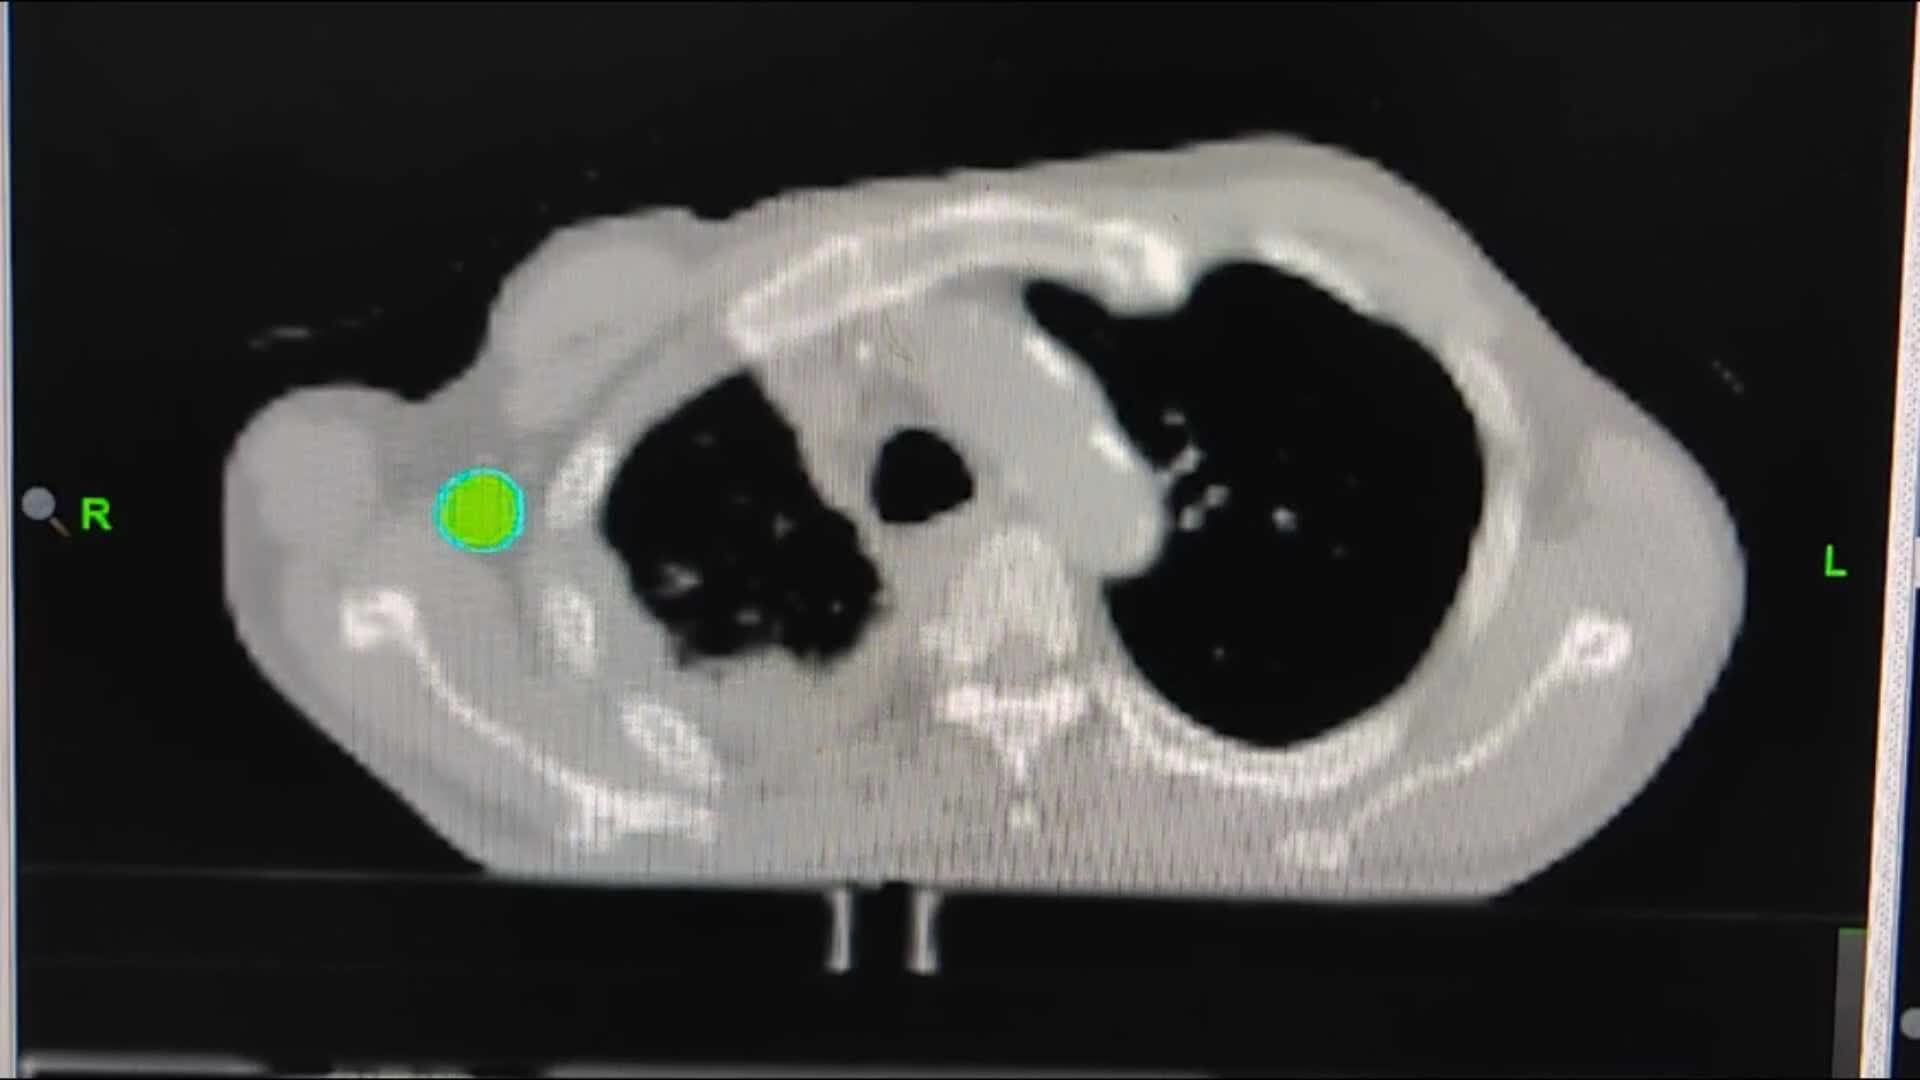

1例(男/74岁)膀胱癌多发转移(肺、骨、肝、脾、胸膜、纵隔、腹膜后、皮肤等)-TOMO放疗

郭某某(BS),男,74岁(出生时间:1949-02-01)

患者主要是右边手术切口及周边疼的厉害,右侧胁肋部疼可以触及肿块,现在说偶尔感觉右肺内也会扯的疼。